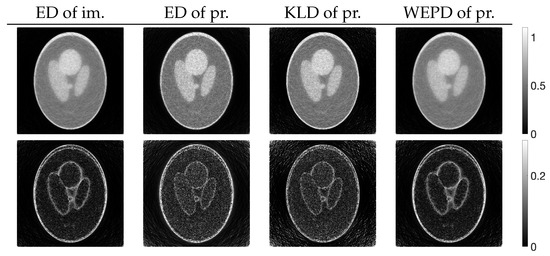

We examined the properties of reconstruction for low-frequency and high-frequency images using disk and chessboard phantom images shown in Figure 1b and Figure 1c, respectively. Figure 6 plots the changes in the evaluation function and parameters. The results for the disc phantom were qualitatively similar to those obtained for the Shepp–Logan phantom, while the results for the chessboard phantom had different characteristics. This indicates that the proposed method should work appropriately not only for generic phantoms like the Shepp–Logan and disc phantoms, but also for geometric patterned images such as the chessboard. The reconstructed images and subtraction images at the maximum iteration number N are presented in Figure 7, and the density profiles in the column direction at the 102nd row of the images are shown in Figure 8. in the figure represents the index that satisfies the equation for the column of the 102nd row of pixels, which is given by . The low-frequency images reconstructed by PXEM and PREM show a similar reduction in the randomness of the density values in the flat regions as PDEM, whereas the reproducibility of the edges in the high-frequency images is comparable to that of MLEM, with a higher contrast compared with PDEM. This is evident not only visually but also quantitatively. Table 1 shows the standard deviation of the subtraction images in the reconstruction of the disc phantom and the contrast of the reconstructed images of the chessboard phantom. Contrast was determined as the difference between the mean high and low intensities. The results indicate that PXEM and PREM performed the parameter estimation appropriately so as to achieve an ideal standard deviation and contrast for objects that should exhibit both flat and steep characteristics.

Figure 7.

Images reconstructed from (a) disc and (b) chessboard phantom images using MLEM, PDEM, PXEM, and PREM (upper) and their corresponding subtraction images (lower).